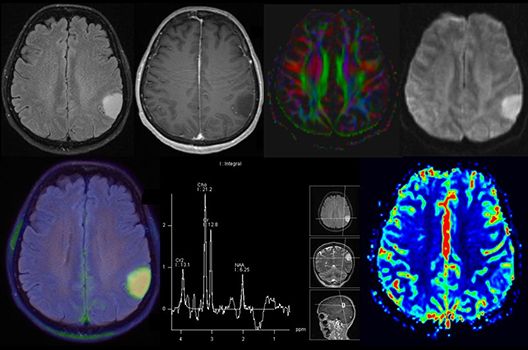

Die Schwerpunkte in der MR-Forschung liegen in der multiparametrischen und funktionellen Bildgebung bei onkologischen und anderen, neuroradiologischen Fragestellungen und umfassen die Anwendung modernster MR-Verfahren sowie die Untersuchung an Hochfeld-Geräten.

Die Magnetresonanztomographie (MRT) ist ein Verfahren, bei dem durch magnetische Kräfte Bilder des Körperinneren angefertigt werden. In der Neuroradiologie können manchmal kleinste Veränderungen schwere Folgen haben; daher forschen wir an der Entwicklung hochauflösender MRT-Sequenzen, mit denen diese Prozesse und auch einzelne Nervenfaserbahnen sichtbar gemacht werden können. Darüber hinaus sind bei vielen Erkrankungen des Gehirns die Blutgefäße betroffen. Daher arbeiten wir an der Neu- und Weiterentwicklung von MRT-Sequenzen zur Darstellung der Blutgefäße und zur Blutflussanalyse (sog. „Angio-MRT“). Einen besonderen Forschungsschwerpunkt unserer Klinik stellen die MR-Protonenspektroskopie und die funktionelle MRT dar, mit denen die Analyse einzelner chemischer Substanzen im Hirngewebe oder die Darstellung ausgewählter Hirnfunktionen möglich ist.

Die Hybridbildgebung mittels PET/MRT spielt insbesondere in der onkologischen Bildgebung eine wichtige Rolle. Eine mögliche Fragestellung ist die Unterscheidung zwischen einem Tumorrezidiv oder therapeutisch assoziierten Veränderungen insbesondere dann, wenn diese Frage mittels MRT alleine nicht beantwortet werden kann.

Die bildgebende Diagnostik und Verlaufsbeurteilung von Tumoren des Nervensystems ist einer der klinischen und Forschungsschwerpunkte unserer Abteilung. Eine besondere Bedeutung kommt der Hybrid-Bildgebung zu. Das Universitätsklinikum verfügt über einen integrierten Ganzkörper-PET/MRT-Scanner, der die Vorteile der MRT-Bildgebung und der Positronenemissionstherapie (PET) vereinigt. Aufgrund der langjährigen klinischen Arbeit und Forschungstätigkeit mit diesem Gerät hat die Neuroradiologie Tübingen maßgeblich zur Etablierung dieses Verfahrens beigetragen. Auch weiterhin forschen wir intensiv an neuen Methoden zur frühen Einordnung von Tumoren und insbesondere Tumorrezidiven, die mit anderen Methoden häufig nicht erfasst werden können.